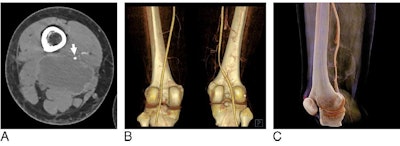

Visualization of a soft-tissue myofibroblastoma near the femoral artery of a 25-year-old woman using CT angiography (A), traditional volume rendering (B), and cinematic rendering (C). Image courtesy of Li et al. CC BY-NC 4.0.Two musculoskeletal radiologists with at least nine years of experience examined the imaging data from CTA and the two advanced visualization techniques. Approximately 58% of the patients were male, and their average age was 49. In all, 21% of patients had tumor invasion based on the reference standard, the confirmed presence or absence of tumor invasion during surgery.

The radiologists were able to identify tumors invading major vessels on the cinematically rendered CT scans with nearly the same accuracy as on the CTA and volume-rendered scans. There were no statistically significant differences between the three techniques.